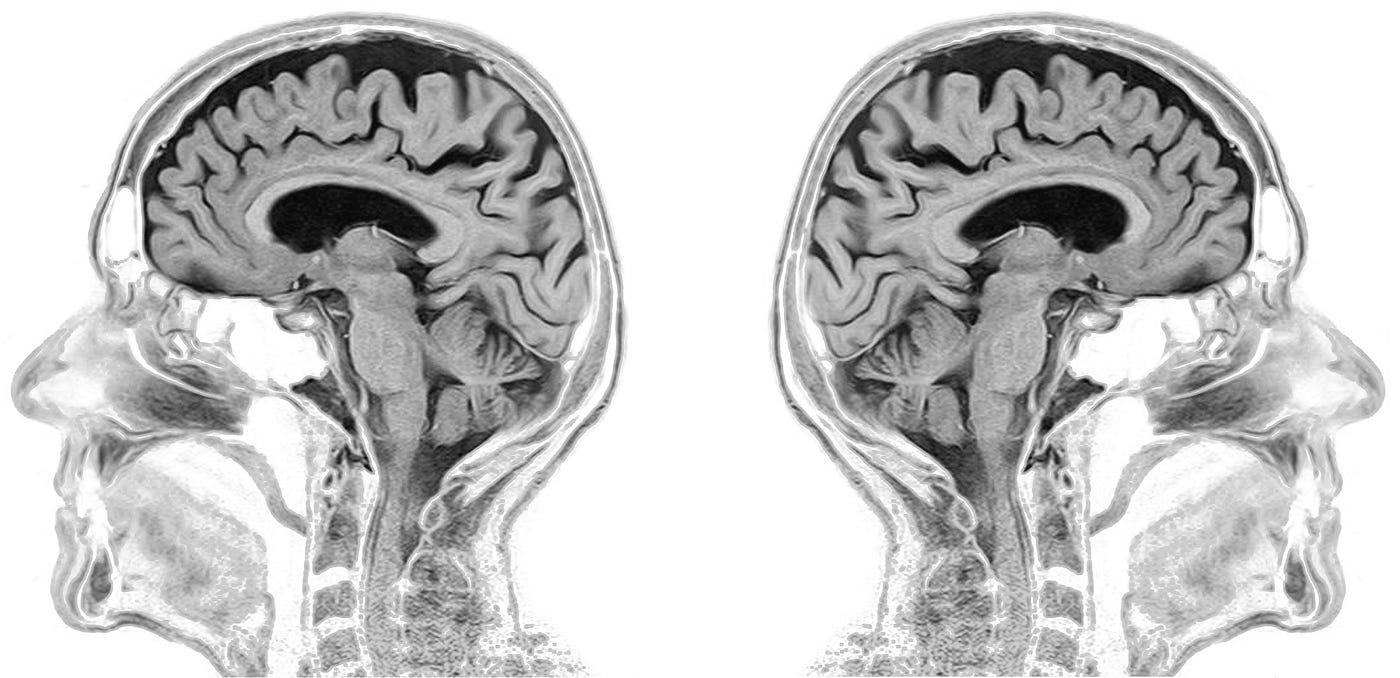

ensure that the voxels are isotropic, i.e. The hippocampus is responsible for accessing memory which is often one of the first functions to noticeably. align the anatomical MRI or functional volume along the x,y,z axis, i.e. It can measure the size and amount of cells in the hippocampus, an area of the brain that typically shows atrophy (shrinkage) during the course of Alzheimers disease.

We disclaim all responsibility for the professional qualifications and licensing of, and services provided by, any physician or other health providers posting on or otherwise referred to on this Site and/or any Third Party Site. The segmentation, detection, and extraction of infected tumor area from magnetic resonance (MR) images are a primary concern but a tedious and time taking task performed by radiologists or clinical experts, and their accuracy depends on their experience only. Learn How to Read Your MRI The shoulder is an incredibly complex joint and when you put it into 3D space through the power of MRI imaging, it can be pretty difficult to figure out where all of the components described above are located. An MRI can provide the ability to view the brain with 3D imaging. When your body is placed in the magnetic field, these atoms align with the field, much like a compass points to the North Pole. Your body is made up of millions of hydrogen atoms, which are magnetic. MedHelp is not a medical or healthcare provider and your use of this Site does not create a doctor / patient relationship. An MRI scan works by using a powerful magnet, radio waves, and a computer to create detailed images. It is not intended to be and should not be interpreted as medical advice or a diagnosis of any health or fitness problem, condition or disease or a recommendation for a specific test, doctor, care provider, procedure, treatment plan, product, or course of action. Teaching point - Normal zonal anatomy: Axial T2-weighted, sagittal T2-weighted and transversal T1-weighted images of a 67-. Radiology PowerPoint Tip Xray of the Week Week 49 Have you ever wondered how to get a scrollable image stack of CT or MR images on a single PowerPoint slide. The Content on this Site is presented in a summary fashion, and is intended to be used for educational and entertainment purposes only.